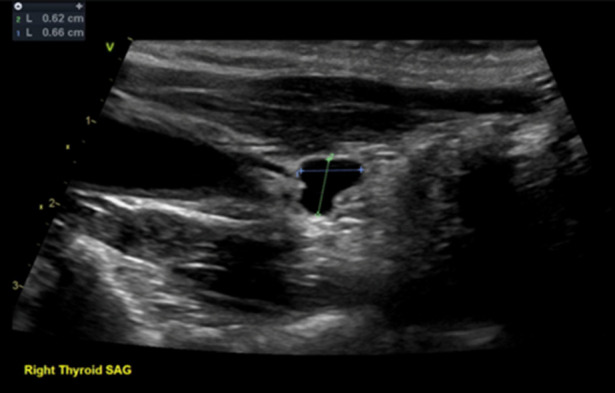

Abstract Image